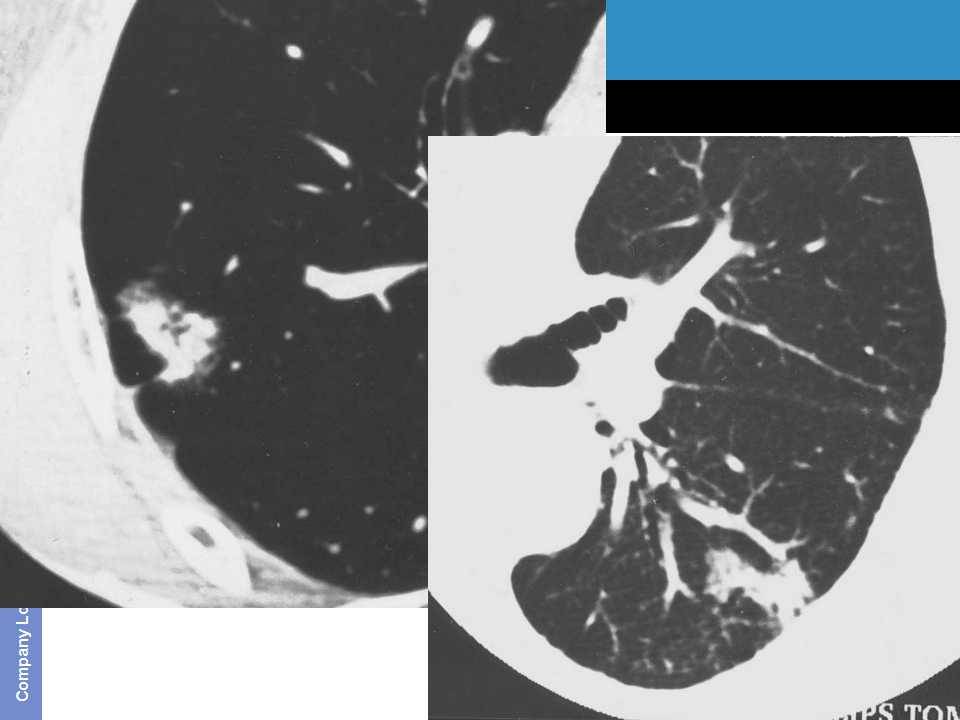

肺癌影像诊断